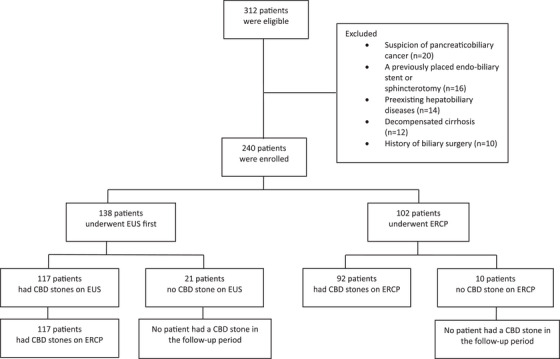

The study flowchart (Figure 2) shows 138 patients undergoing initial EUS, with 117 proceeding to ERCP after CBD stones were detected; stones were confirmed in all 117 cases. Among 21 EUS‐negative patients, none developed CBD stones during follow‐up. Of 102 ascending cholangitis patients undergoing direct ERCP, 92 (90.2%) had CBD stones, while 10 (9.8%) did not, with no subsequent stone detection in follow‐up.